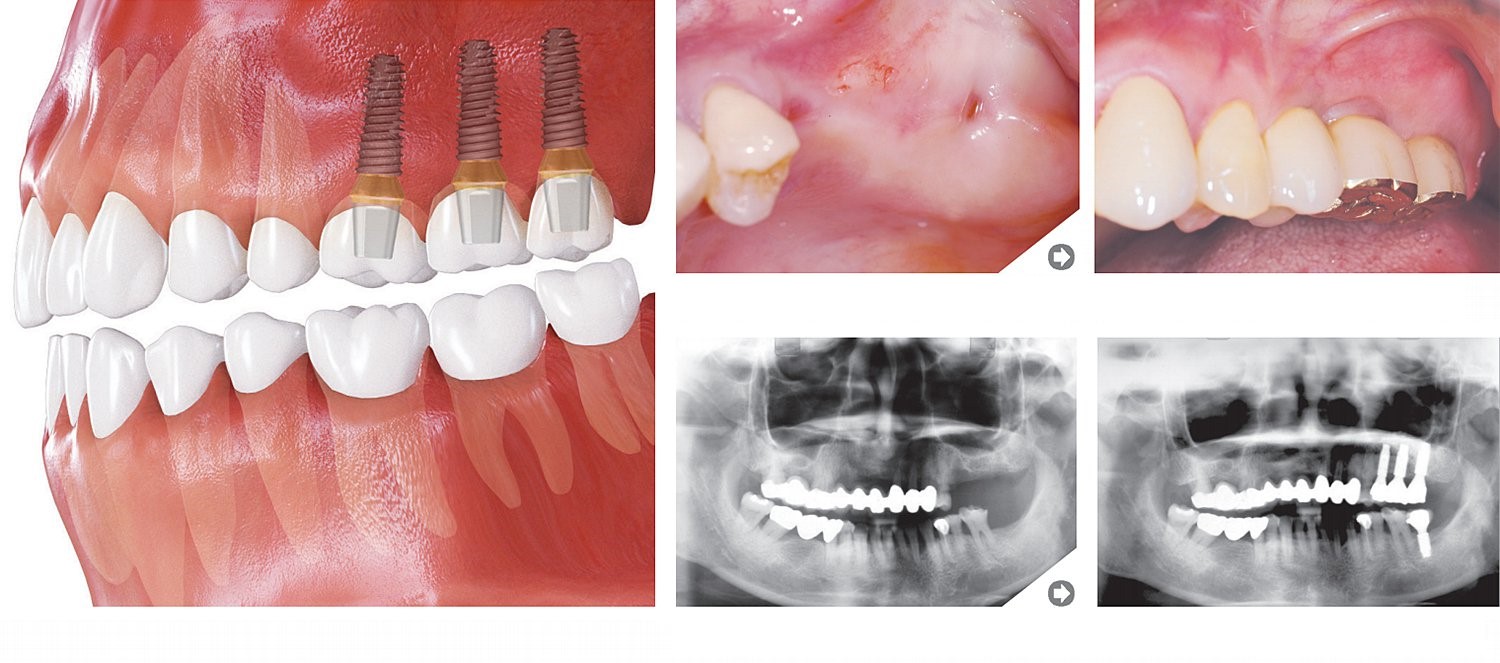

Trūkst pāris zobu

Augšējie molāri

Apakšējie molāri